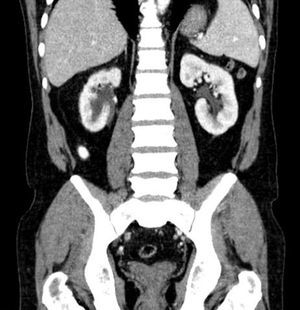

En la TAC aportada se apreciaba una ectasia pieloureteral derecha grado ii/iv, producida por una lesión polipoidea en la pelvis renal que se extendía al uréter proximal, así como lesiones hepáticas (figs. 1-3). La citología urinaria era negativa para células neoplásicas, y la cistoscopia no reveló la presencia de lesión vesical concominante.